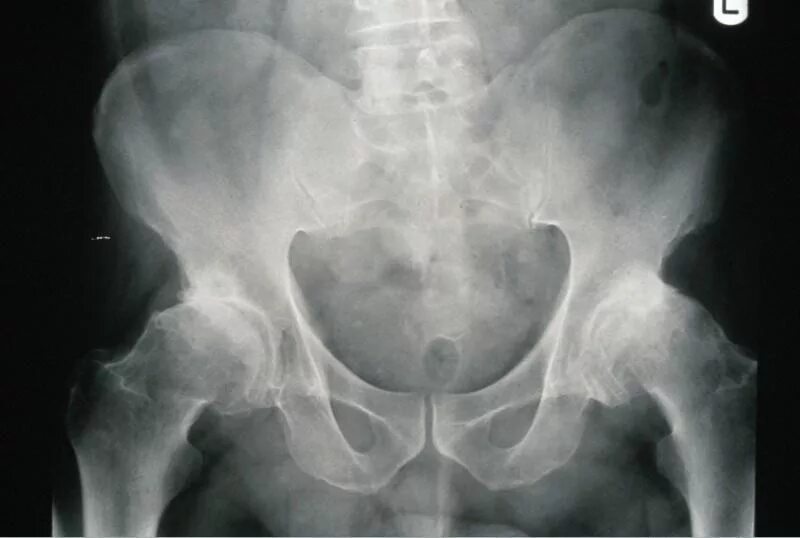

Доа тазобедренного сустава 2 степени